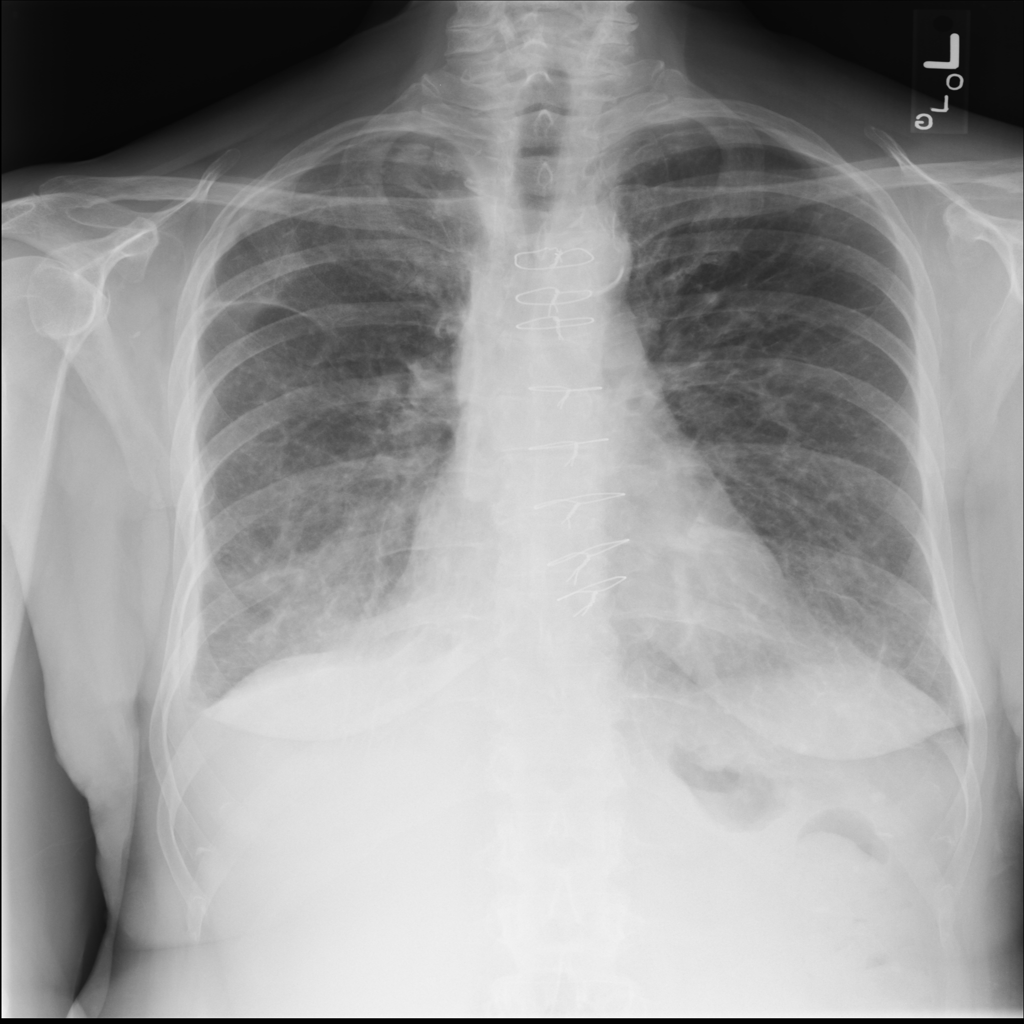

PAT-4639 · IMG-021Effusion

PAT-4639 · IMG-021

PA